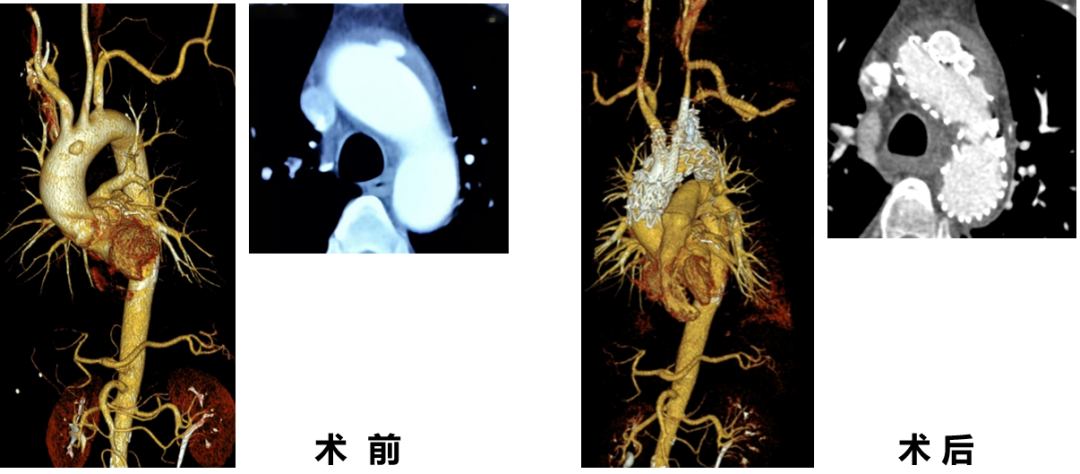

WeFlow-Arch™病例展示

★ 病例1:模块内嵌分支胸主动脉覆膜支架系统

★ 病例2:模块内嵌分支胸主动脉覆膜支架系统

术前

术后